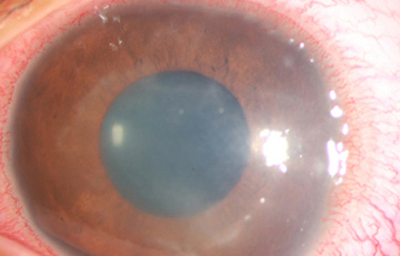

Superficie corneal irregular y grisácea, (Fig. 1, 2) con opácidades granulares en parche y formación de líneas epiteliales elevadas de aspecto granular (Fig. 3), que pueden arborizar dando imágenes de pseudodendritas. Opacidades superficiales satélites. (Figura 4) Inyección ciliar. Ulceración epitelial variante. (Figura 5).

Fig. 1 Síntomas de 15 días evolución